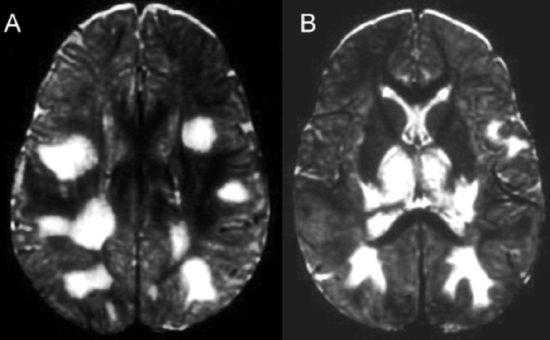

Контрастная МРТ является чувствительным методом для выявления энцефалита, вызываемого ВПГ, на ранней стадии; при исследовании выявляется отек в орбитофронтальной и височной областях, которые наиболее часто поражаются ВПГ. При прогрессирующей мультифокальной лейкоэнцефалопатии МРТ-исследование позволяет выявить признаки демиелинизации, а при энцефалите Западного Нила и восточном лошадином энцефалите - изменения со стороны базальных ядер и таламуса. МРТ позволяет также исключить поражения, схожие с вирусным энцефалитом (например, абсцесс головного мозга Абсцесс головного мозга Абсцесс головного мозга представляет собой локальное скопление гноя в веществе мозга. Клиническая картина может включать в себя головную боль, вялость, лихорадку и очаговую неврологическую симптоматику. Прочитайте дополнительные сведенияДля диагностики ВПГ-энцефалита КТ является менее чувствительным методом по сравнению с МРТ, но также может оказаться полезным ввиду своей большей доступности и возможности исключить состояния, которые могут сделать проведение люмбальной пункции рискованным (например, объемные образования, гидроцефалия, отек головного мозга).

При клещевом энцефалите типичными местами поражения будут базальные ганглии, мозжечок, таламус. При болезни Лайма под корой и вблизи желудочков мозга выявляют очаги инфаркта мозга.